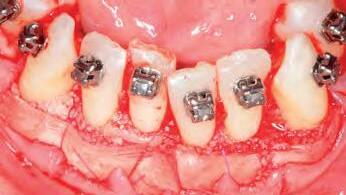

Ortodoncia y Periodoncia en Sinergia: Manejo del Paciente Periodontal y Modificación del Fenotipo en Tratamientos Ortodóncicos

Dr. Javi Vilarrasa y Dr. Jordi Vilarrasa

SESIÓN 1 | 9:30-13:30

Ortodoncia en Pacientes Periodontales. Casos clínicos

• Biología del movimiento dentario con ortodoncia.

• Consideraciones biomecánicas en el tratamiento ortodóncico del paciente periodontal.

• Diagnóstico periodontal en pacientes ortodónticos: herramientas y criterios clave.

• Mantenimiento periodontal durante y después del tratamiento ortodóncico.

• Evaluación y clasificación del fenotipo periodontal.

• Influencia del grosor de encía y hueso en la planificación ortodóncica.

• Movimientos ortodóncicos críticos en función del fenotipo periodontal.

SESIÓN 2 | 15:00-19.30

Modificación del Fenotipo Periodontal asociado a Corticotomías. Casos clínicos

• Bases biológicas de la aceleración del movimiento ortodóncico mediante corticotomías.

• Técnicas quirúrgicas para la modificación del fenotipo periodontal en ortodoncia.

• Indicaciones y protocolos clínicos para la combinación de ortodoncia y corticotomías.